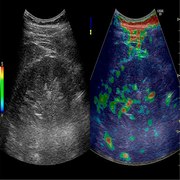

Currently elastography has wide applications in assessing breasts, thyroid, prostate, and liver. Increasing number of ongoing studies are expected to increase its applications in diagnosis of various conditions such neurodegenerative disorders and chronic kidney diseases. It has shown promising results for its use in assessment of kidney health during and after transplantation.

•By modality, the ultrasound segment is predicted to register significant growth during the forecast period owing to advantages such as low price, accessibility, and high degree of measurement for tissue deformation